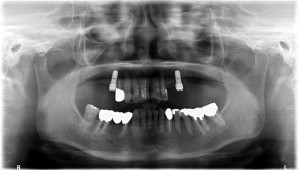

上左右の奥歯を失ってしまったため、保険の入れ歯を入れたが、違和感が強く、しっかり噛むことができないため、インプラントを併用した入れ歯を作ることで違和感なく、しっかり噛むことができるようになった。 また通常の入れ歯は、はずれないようにするため金属のバネを歯に引っ掛けるため見た目も悪いが、インプラントによって固定されているためバネもなく、見た目も非常に良いものとなっている。

術後レントゲン写真